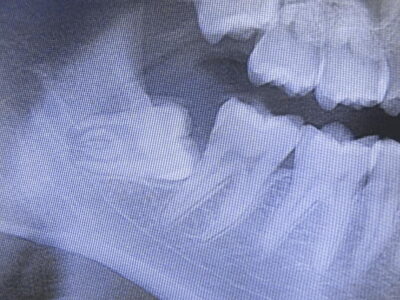

親知らず

親知らずをお持ちの方は、10代後半から30歳くらいまでに症状が現れることが多く個人差があります。顎(あご)の骨の中に完全に埋まっていたり、半分埋まっていたり、斜めに生えていたりと色々です。症状としては、顎が痛くなったり歯茎が腫れたり、食べ物がつまったりします。腫れや痛みを繰り返すものは、周囲に炎症が広がっている可能性が考えられ、ばい菌の侵入や虫歯が進行している可能性があり、それらを含めお困りの際は、速やかに当医院に相談して頂ければと思います。また当医院では、親知らずの抜歯を行うにあたり、歯の形や顎の中の神経などの位置関係を知るために2次元的なレントゲン写真だけでは難しい場合、CT撮影行い3次元的な画像にて安全評価を行いリスクの低減・回避を行う事があります。ただし状態によっては、大きな病院を紹介させて頂き、そちらで抜歯をして頂く場合もあります。

(※ 親知らずがほかの歯と同じ様に生え症状がない方、他の部位に移植・再植予定のある方などは、抜歯を行わないこともあります。)